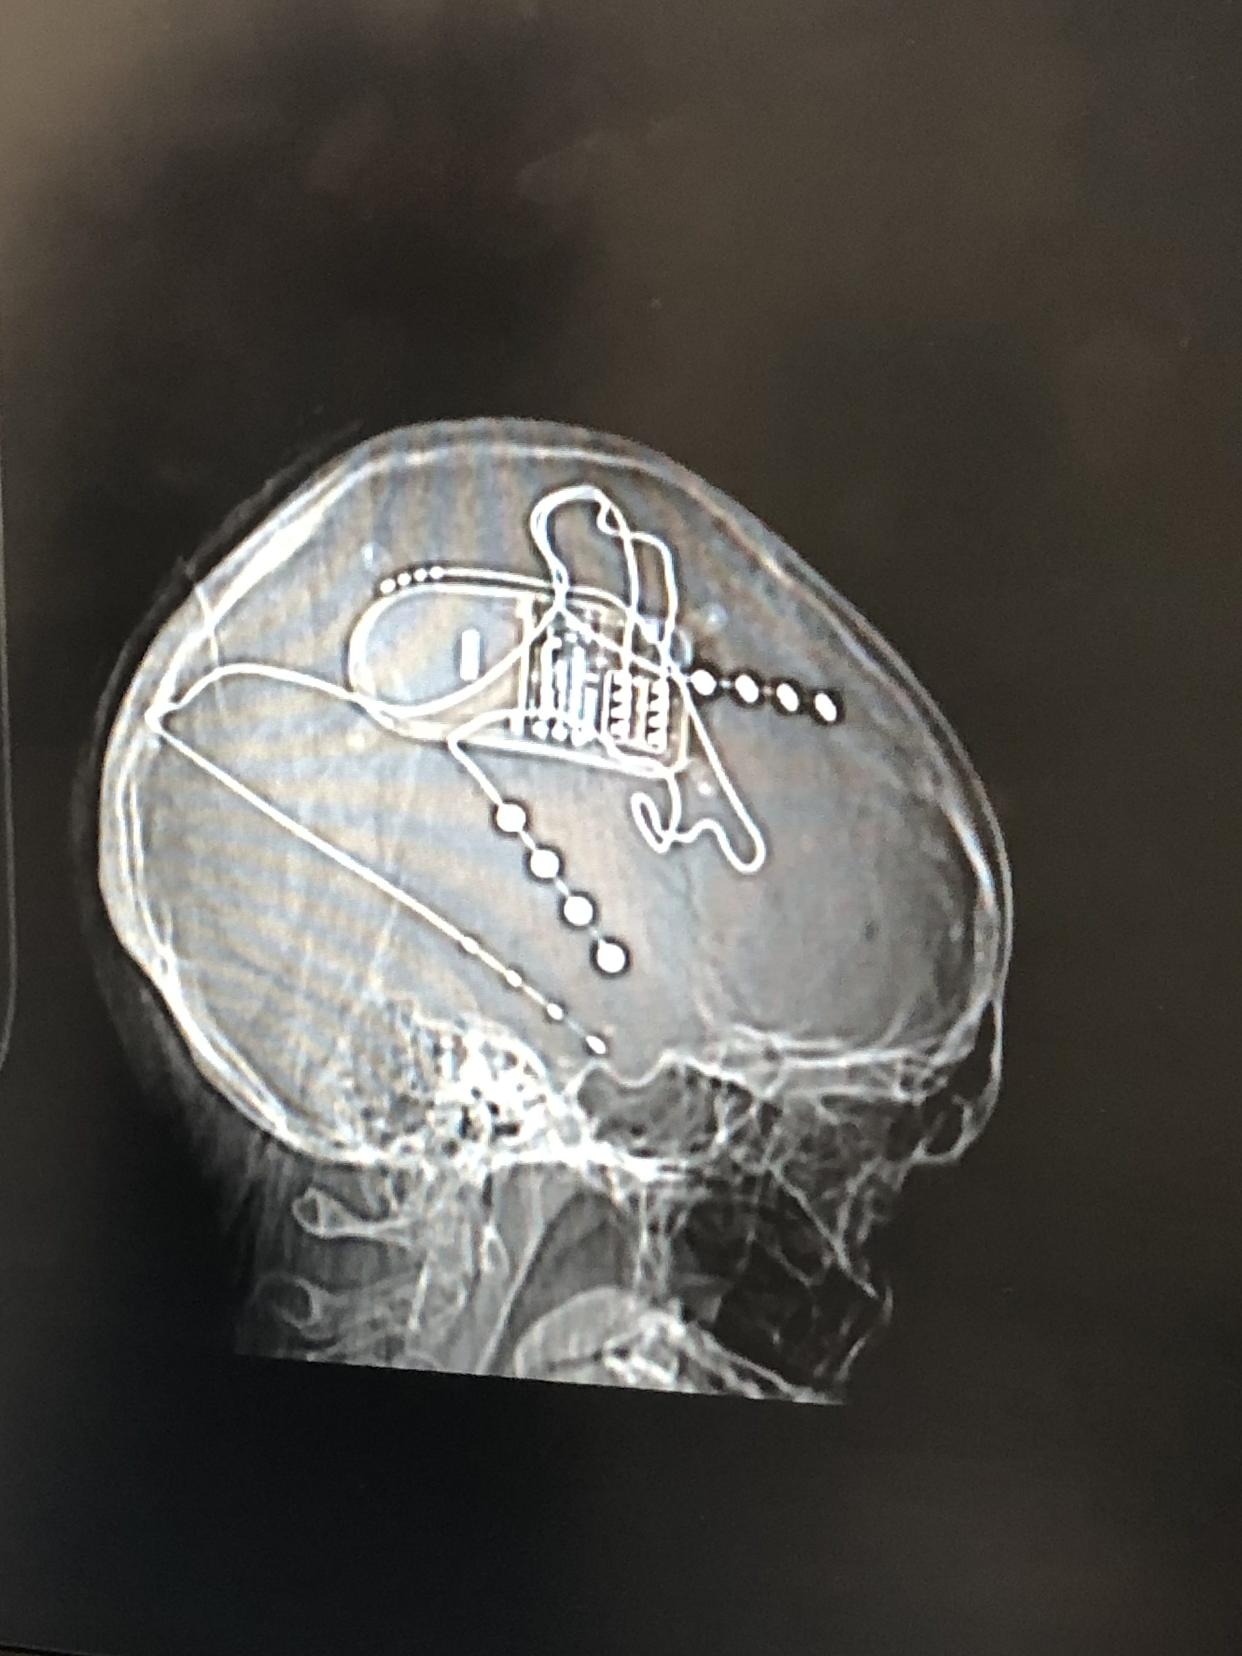

The NeuroPace implant prevents Hoffman’s seizures. By Ariel Hoffman

The device inside Hoffmann’s brain. By Ariel Hoffman

To prevent accidents, surgeons planned to implant a neurostimulation device—like a pacemaker—in Hoffman’s head. Thin wires would be placed in the danger of grabbing her brain, detecting abnormal activity and delivering short pulses of electricity to intervene.

Hoffman used stereo electroencephalography to determine where her seizures began in the brain. By Ariel Hoffman

The next step was stereo electroencephalography (SEEG), in which surgeons drilled 14 small holes in her head and placed sensors directly in her brain to see where the seizures were occurring.